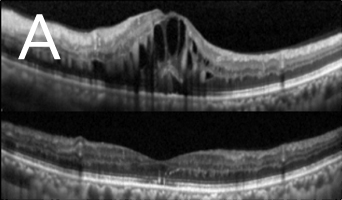

黄斑点视网膜前膜增生(图2)是本港常见眼疾之一,治疗方法包括切除玻璃体及移除前膜。采用内界膜去皮最新治疗能让患者的视力获得改善,而接受初次手术後复发率属低。

![]() 图2:深近视人士患上黄斑点视网膜前膜病变(手术前摄)。 |